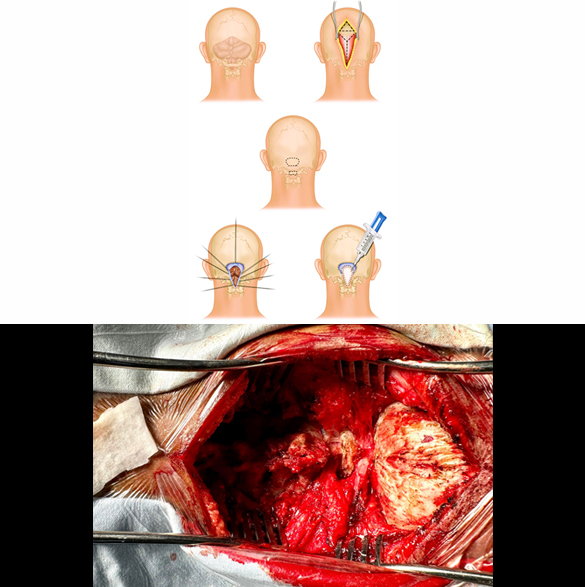

Brain Tumor Surgery

Most of the brain tumors are treated with surgery first. They may need additional treatment with radiotherapy, chemotherapy or hormonal therapy. Brain tumor surgery is a specialized and delicate procedure, requiring good preoperative and postoperative management. Brain tumor surgery generally requires opening the cranium/skull (craniotomy) and tumor removal (excision). Surgical excision can be; gross total resection (GTR), maximum safe resection (MSR), partial resection, decompression, biopsy. The outcome of brain tumor surgery depends on the site, size and type of the tumor inside the brain. Few complications of the brain tumor surgery may be wound infection, intracranial bleeding, seizures, meningitis, and weakness or paralysis.